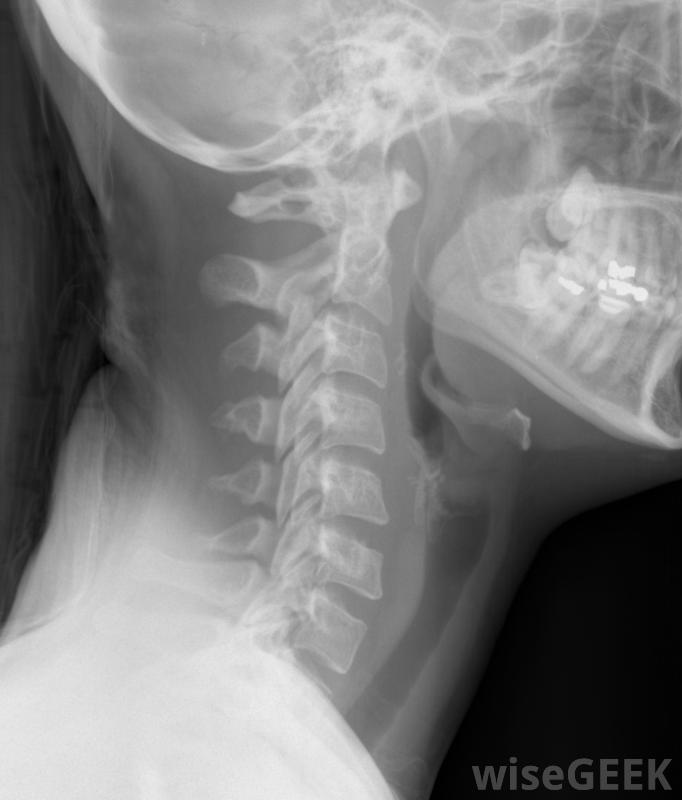

包括颈椎在内的颈部X光片。导致颈神经根病的原因很多。随着年龄的增长,它们的骨骼和软组织发生退行性改变。脊柱椎间盘失去水分并开始塌陷,从而导致椎骨之间的间隙变窄。小关节(位于相邻椎骨之间和后面的关节)由于压力增加而受到刺激而变大,因此压迫神经引起疼痛。